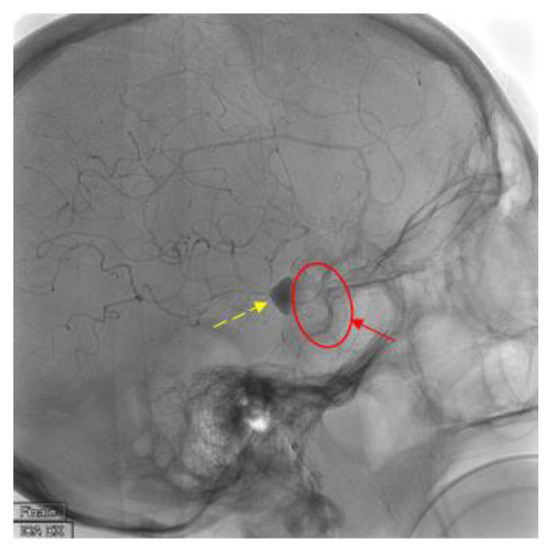

2. Case Presentation